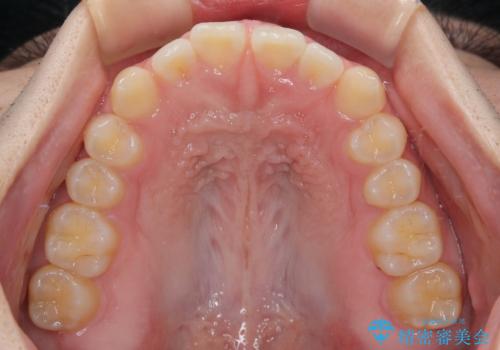

- 「前歯のすきっ歯が気になる」「食べ物が歯の間に詰まりやすい」とのお悩みで来院された20代男性の患者様です。

歯と歯の間に隙間がある**空隙歯列(すきっ歯)**は、見た目の問題だけでなく、食片圧入による歯肉の腫れや、隣接面う蝕のリスク増加につながることがあります。

患者様は「できるだけ目立たない矯正治療」を希望されていたため、インビザラインを用いた治療計画を立案しました。

インビザラインは透明で装着していても気づかれにくく、日常生活やお仕事への影響を最小限に抑えながら治療を進めることが可能です。

診査により舌突出癖が認められました。この癖は、すきっ歯の原因となるだけでなく、矯正後の後戻りリスクを高めます。

そこで矯正治療と並行して**MFT(口腔筋機能療法)**を実施し、舌や口周囲筋の正しい使い方を習得していただきました。